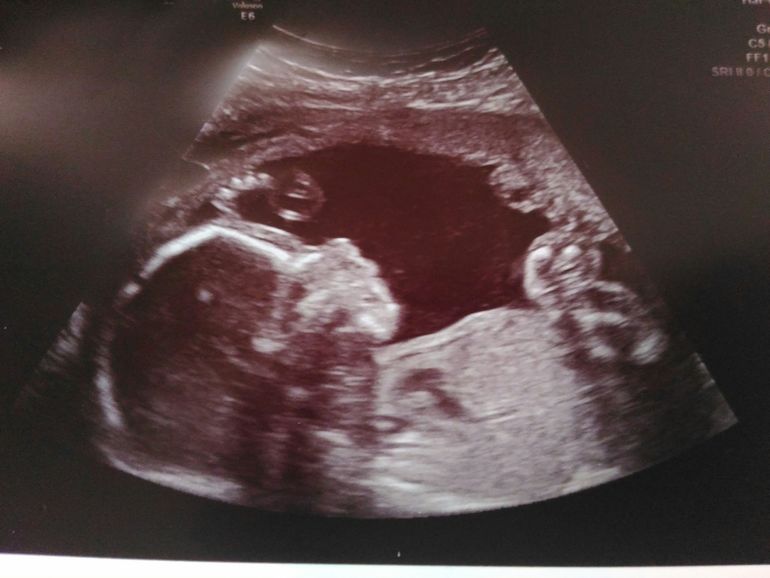

на фото видно ножки, яйки и пипку!

О малыше: мальчик, 474 грамма, 26 см.

Все соответствует нормам. Малыш шевелится после употребления любой еды.